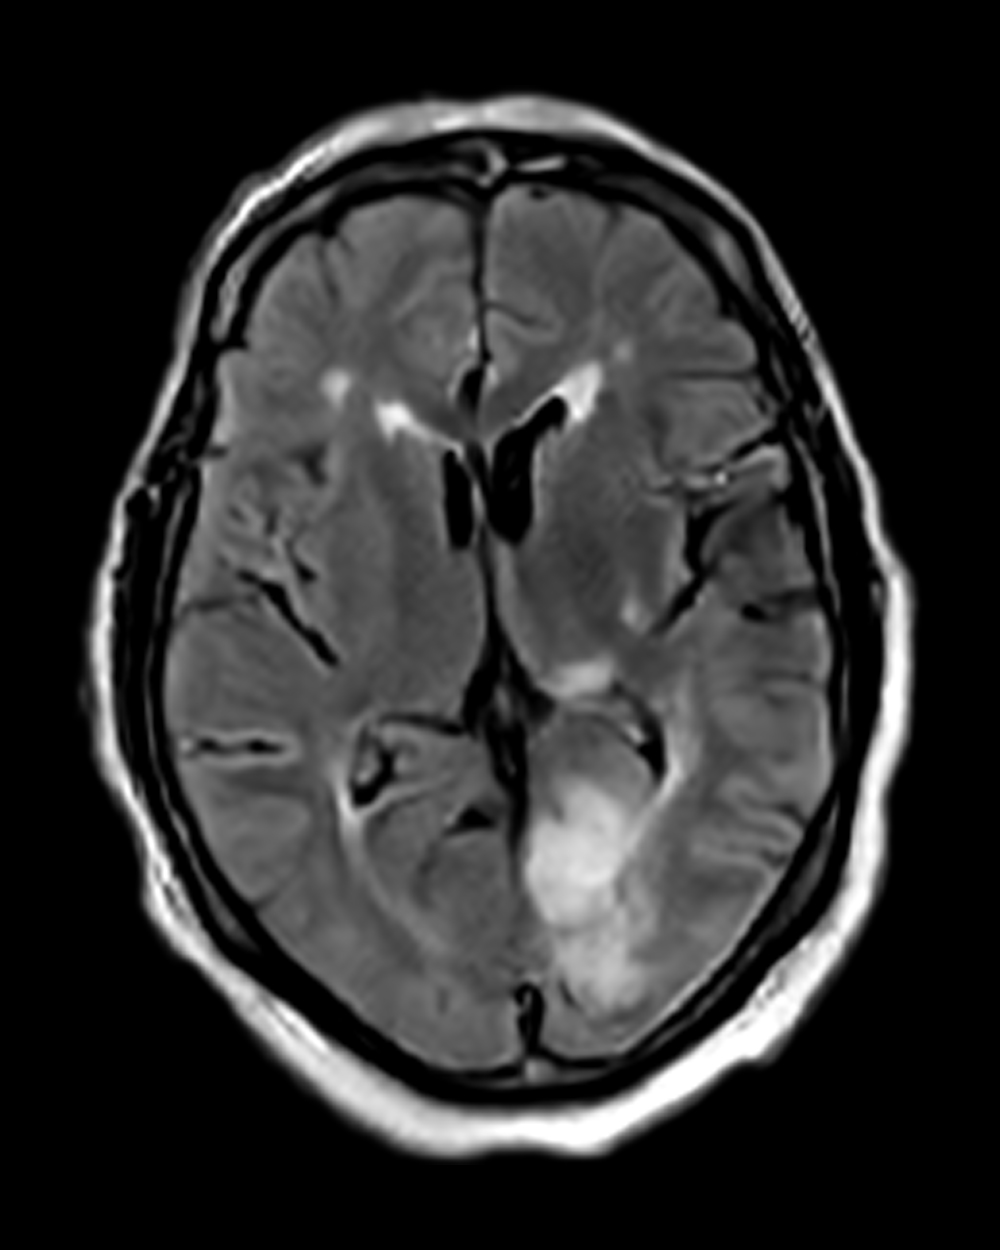

A tissue clock for identifying treatable strokes

For wake-up strokes or unknown onset, DWI-FLAIR mismatch can serve as a tissue-based marker to help determine stroke age—critical for guiding treatment decisions.

Right Anterior Choroidal Infarct

Patient Profile

63-year-old patient with a history of diabetes and hypertension. Presented to the ED with acute-onset left-sided weakness and sensory disturbance involving the face and extremities.

Left Posterior Cerebral Infarct

72-year-old patient presented to the ED with acute-onset visual disturbance and right-sided weakness.

Portable MRI

The Swoop system was driven to the patient’s bedside and ready to scan within minutes

Stroke Detected

Swoop system images allowed clinicians to confirm infarcts

Triage

Patients were triaged to stroke units for management and monitoring